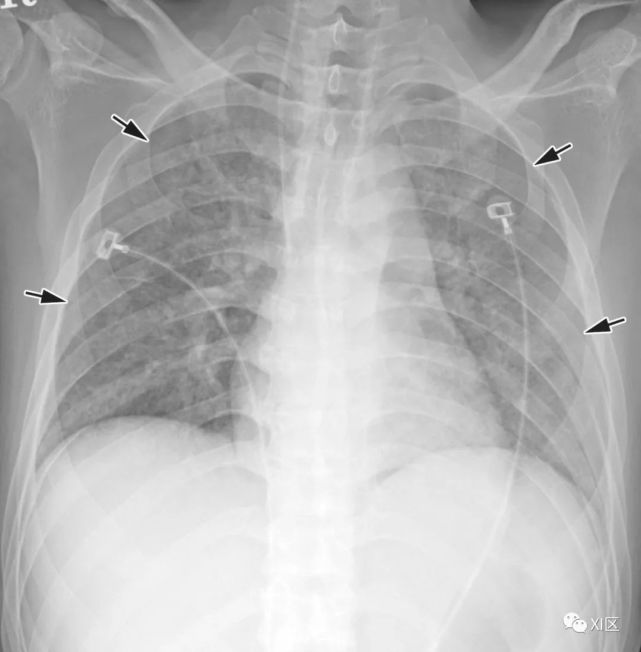

图16 58岁女性急性髓系白血病伴有发热,并发呼吸道合胞病毒肺炎。

(上) 初诊胸片显示双肺多发不规则结节状支气管周围气隙或GGO(箭头),少量双侧胸腔积液。在同一天在较低的气管水平(中)和叶间区水平(下)上获得的轴位胸部CT图像显示多个不规则的结节影和树芽征,沿支气管血管束斑片状实变,支气管壁轻度增厚。

Koo H J , Lim S , Choe J , et al. Radiographic and CT Features of Viral Pneumonia[J]. Radiographics, 2018, 38(3):719-739.